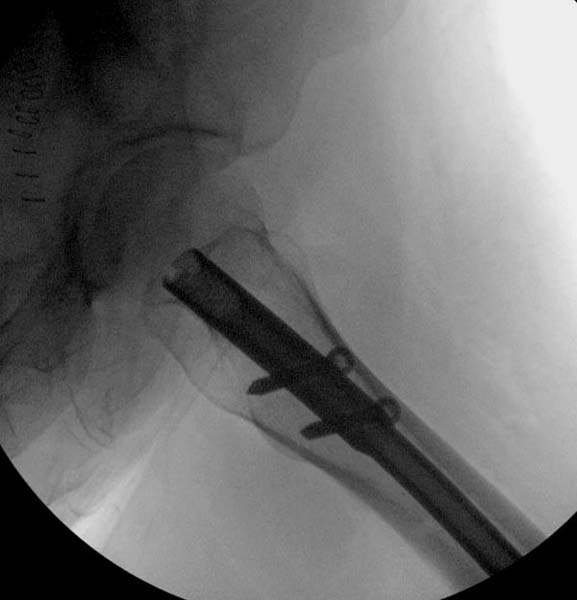

Больная стабильная после хирургических мероприятии и получив добро, приступили к закрытому вправлению таранной кости с укладкой наружного фиксатора. Затем укладка больную на бок и открытый остеосинтез перелома-вывиха головки бедра.

Трудно выбрать приоритет, когда имеется одинаковые по значимости, по сложности повреждения и с вовлечением различной локализации. У пожилых переломо-вывих головки бедра можно было бы проигнорировать, но у молодых такое решение привело бы к катастрофе, и поэтому приоритет первичной фиксации отдали решению переломо-вывиха таранной кости и головки бедра.